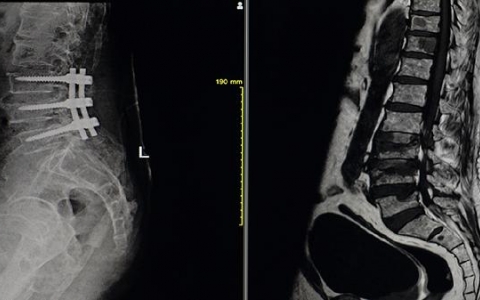

确诊强直性脊柱炎需要结合临床症状、体格检查、实验室检查和影像学检查等多种方法。这种疾病是一种慢性炎症性疾病,主要影响骶髂关节、脊柱关节等部位。为了避免病情延误,

强直性脊柱炎患者是否通过手术治疗能快速恢复,实际上要根据个人的具体病情来决定。对于处于疾病早期的患者,通常药物治疗就能有效控制病情,无需手术。但如果病情已发展到